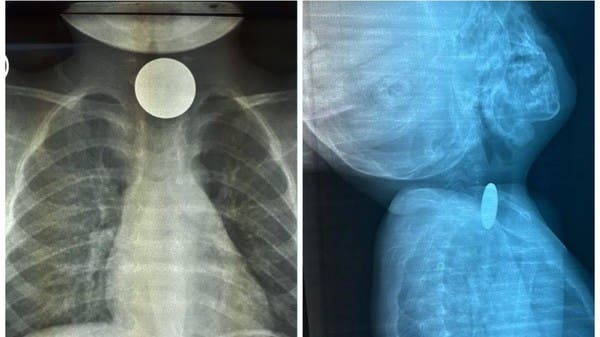

تمكن فريق طبي بمستشفى رابغ العام، من استخراج قطعة معدنية من بلعوم طفل يبلغ من العمر عامين، خلال عملية لم تستغرق أكثر من 10 دقائق.

وأوضحت “صحة جدة” أن الطفل قَدِم إلى طوارئ المستشفى وهو يشكو ابتلاع جسم غريب (قطعة نقود معدنية) كانت قد علقت في منطقة البلعوم؛ مما تسبب في اختناق وعدم قدرة على البلع.

وقرر الطاقم الطبي إجراء عملية عاجلة بالمنظار لإزالة الجسم الغريب، والتي تبين أنها قطعة معدنية نقدية، وقد كُللت العملية بالنجاح دون حدوث مضاعفات وقد غادر الطفل المستشفى وهو بصحة جيدة.